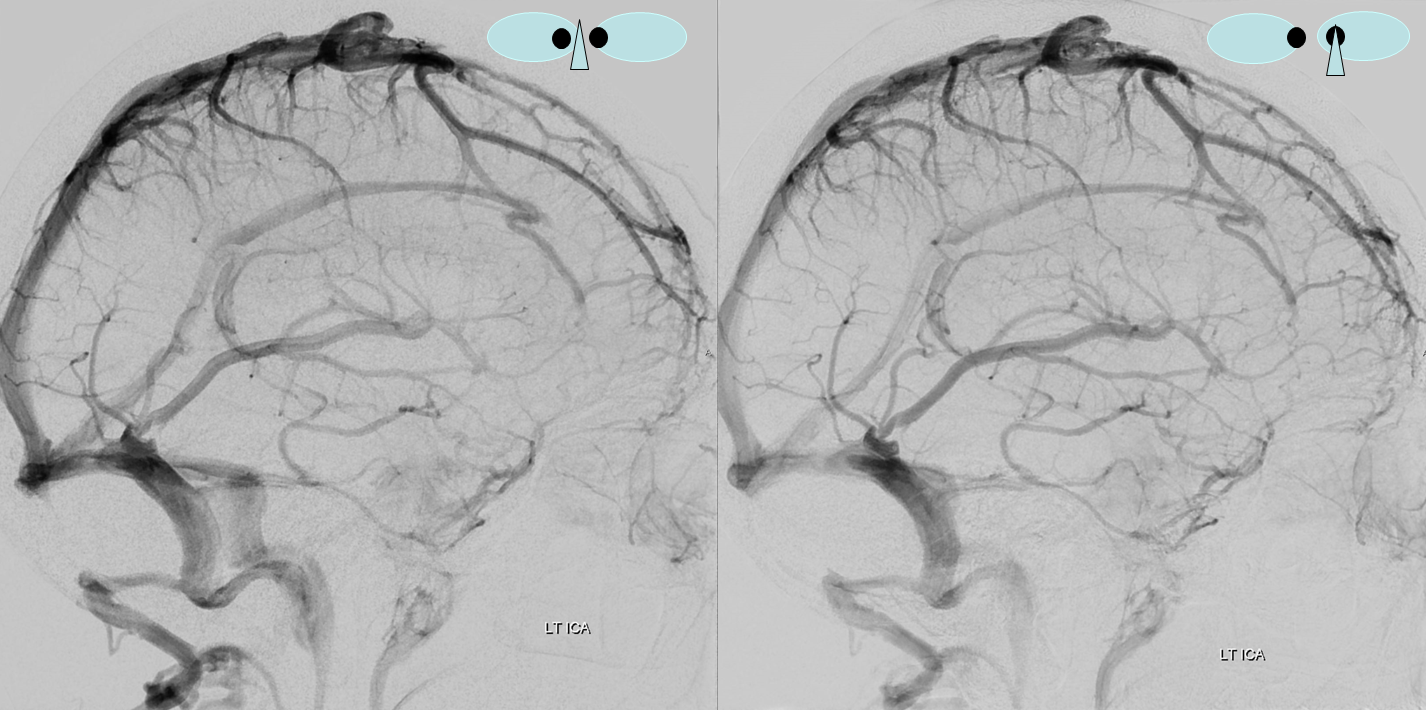

Fenestration of the proximal right transverse sinus, in stereo

Following embolization, resection, recurrence (as frequently the case with childhood AVMs) and gamma-knife, things look good. Stereo, of course.

Following embolization, resection, recurrence (as frequently the case with childhood AVMs) and gamma-knife, things look good. Stereo, of course.